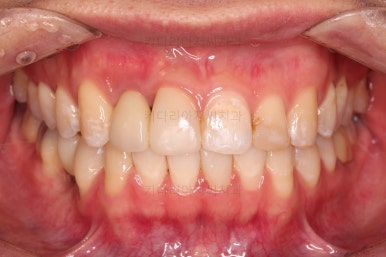

임플란트 완료시 모습인데요.

임플란트 식립부터 완료까지 시간이 걸리다보니 최종 종료까지는 총 19개월이 걸렸습니다.

교합도 잘 맞고 임플란트도 잘 완성되었네요.

매복치아도 손상 없이 잘 배열이 되었고, 교합도 좋게 마무리 되었습니다.